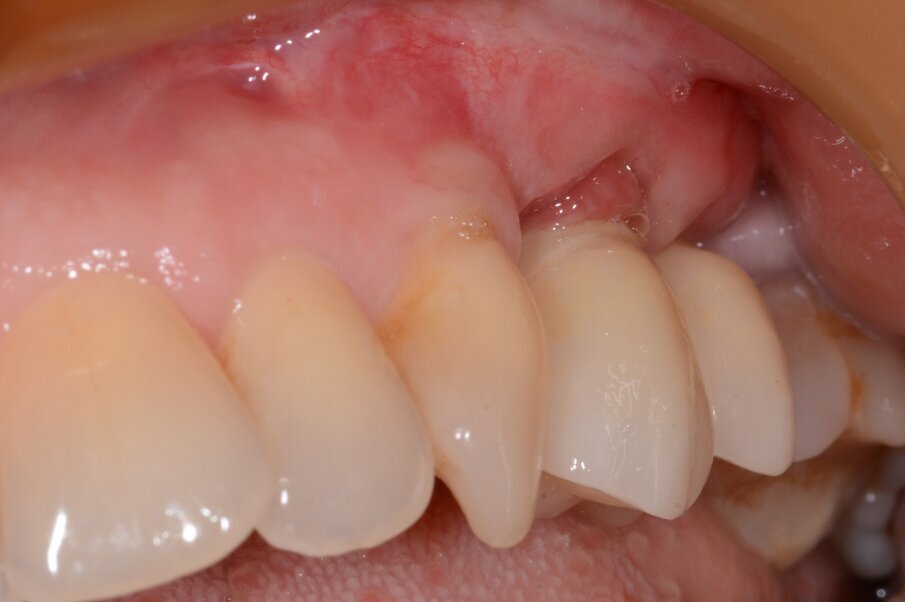

In Case 2, the patient preferred a surgical procedure with bone augmentation, as a consequence of bone graft complication and graft exposure (Figs. 8–12).

Fig. 8: Initial situation.

Fig. 9: Granulation tissue visible after flap elevation.

Fig. 12: Final results with restoration two years post-op.